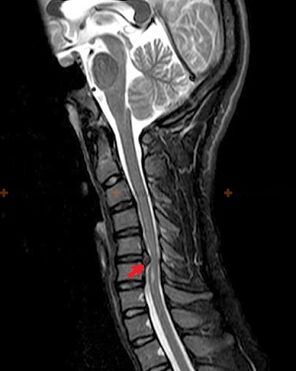

Diagnostik und Röntgenzeichen

Osteochondrose ist eine Röntgendiagnose, da ein detailliertes klinisches Bild nur im Moment der Exazerbation vorliegt, während bei völligem subjektivem Wohlbefinden einer Person Veränderungen in der Wirbelsäule auftreten können. Ohne Röntgenuntersuchung kann nur von einem Verdacht auf Osteochondrose gesprochen werden, da ähnliche Symptome auch durch andere Erkrankungen (Myositis, Wirbelneoplasien ua) verursacht werden können.

Zur Diagnose einer Osteochondrose werden folgende Untersuchungsmethoden eingesetzt: Radiographie (vorzugsweise mit Funktionstests), MSCT und MRT. Die letztgenannte Studie ist am meisten zu bevorzugen, da sie eine sehr klare Visualisierung des Zustands der Zwischenwirbelstrukturen ermöglicht.

Zu den Röntgenzeichen einer Osteochondrose zählen folgende Veränderungen der Wirbelsäule:

- Reduzierte Höhe der Bandscheiben.

- Vorhandensein marginaler Knochenwucherungen.

- Verletzung der Lage der Wirbel relativ zueinander.

- Verformungen von Wirbelkörpern und Bögen usw.

Das Vorliegen der oben beschriebenen Veränderungen sowie durch MSCT und MRT festgestellte Veränderungen in der Struktur der Bandscheibe dienen als zuverlässige Anzeichen für das Vorliegen einer Osteochondrose.